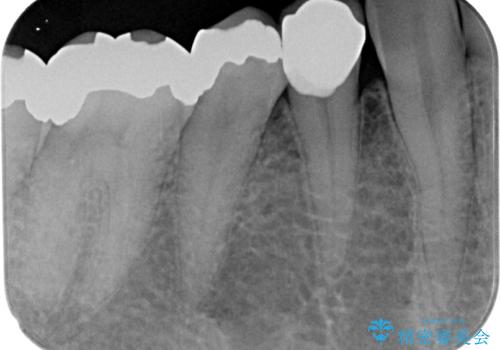

- 右下の銀歯が取れたとのことで来院された患者様です。以前にも取れていたところで、メタルインレーの不適合も認めていたため、次回外れたらオールセラミッククラウンにやり替えていくことを説明していたため、オールセラミッククラウンによる補綴治療を行っていくことにしました。

審美面、機能面共に満足していただけました。

順次、後ろにある不適合のメタルインレーの部位をやり替えていく予定です。